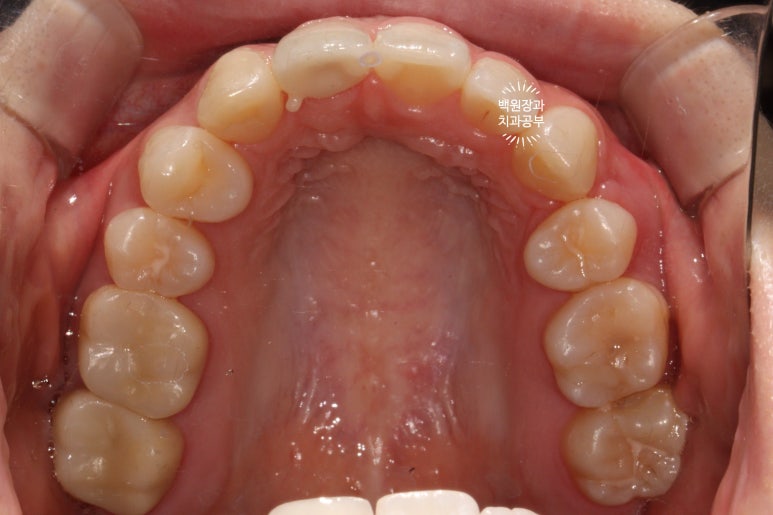

교합면에서 보면, 앞니가 다섯개라는 것이 더 명확해집니다!!!

아마, 어렸을 때 앞니를 잃어버리신 것 같아요. 그래서 작은 어금니도 비대칭으로 왼쪽은 1개 오른쪽은 2개였습니다. 상당히 난이도 있는 교정치료일텐데, 정말 훌륭한 치료결과이긴 했었어요!